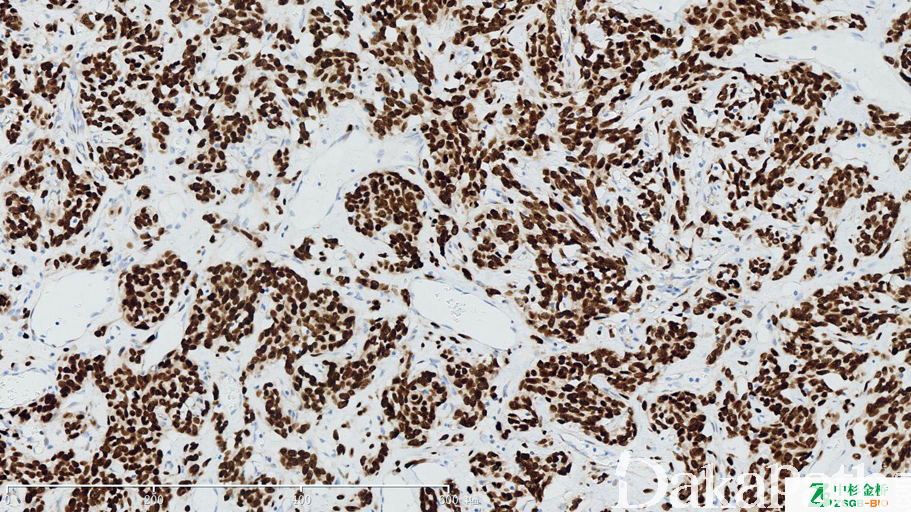

信号传导和转录激活因子 6,应答细胞因子和生长因子受体相关激酶磷酸化,是 IL-4 介导的生物反应,还参与介导的过程中相关的细胞因子 IL-13、IL-4。表达在大多数的正常组织中,呈胞浆、胞核表达。在孤立性纤维性肿瘤/血管外皮瘤中具有 12q13 易位,NAB2 与 STAT6 融合引起 STAT6 在核内强表达。

信号定位: 胞核,胞浆

孤立性纤维性肿瘤(胞核+)的诊断和鉴别诊断。

几乎全部阳性(≥95%的病例阳性): 孤立性纤维性肿瘤